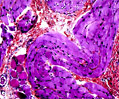

Kidney Stained Tissue